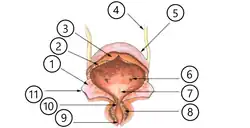

Nach seinem Eintritt in die Harnblasenwand verläuft der Harnleiter zunächst eine kurze Strecke innerhalb dieser Wand (intramural). Dieser intramurale Abschnitt ist 0,5 bis 1 cm lang,[10] nach anderen Angaben 1,5 bis 2 cm.[3] Dann durchbohrt er die Blasenschleimhaut und mündet mit der Harnleitermündung (Ostium ureteris) in das Innere der Harnblase. Die schlitzförmigen Harnleitermündungen sind klappenartig geschlossen, wenn durch sie kein Urin tritt.[3] Der Verlauf in der Blasenwand verhindert bei stärkerer Füllung der Harnblase einen Rückfluss des Urins zur Niere (vesikorenaler Reflux).[11] Die beiden Harnleitermündungen begrenzen mit der unpaaren Harnröhrenöffnung im Inneren der Blase das Harnblasendreieck (Trigonum vesicae).[12]